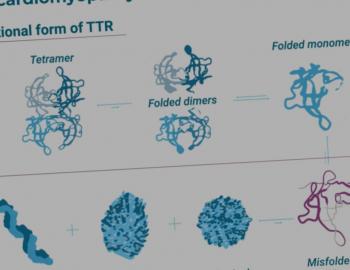

ATTR en erfelijkheids-onderzoek

Cardiale amyloïdose